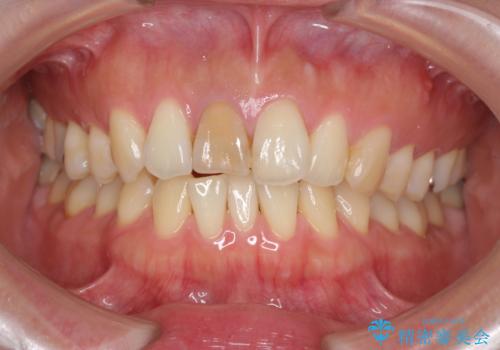

X線検査を行ったところ、共に深い虫歯が原因となり神経が死んでしまっている状態であることがわかり、根管治療を行ったのちセラミック補綴を行っていくこととなりました。

- 32万円(仮歯・ファイバーコア・ジルコニアクラウン×2)費用は治療当時の料金となります

最終的なセラミッククラウンの精度・色調は非常に大事ですが、そこに至るまでの根管内環境の洗浄、ファイバーコアによる緊密な封鎖も長期的な予後に重要であると考えます。